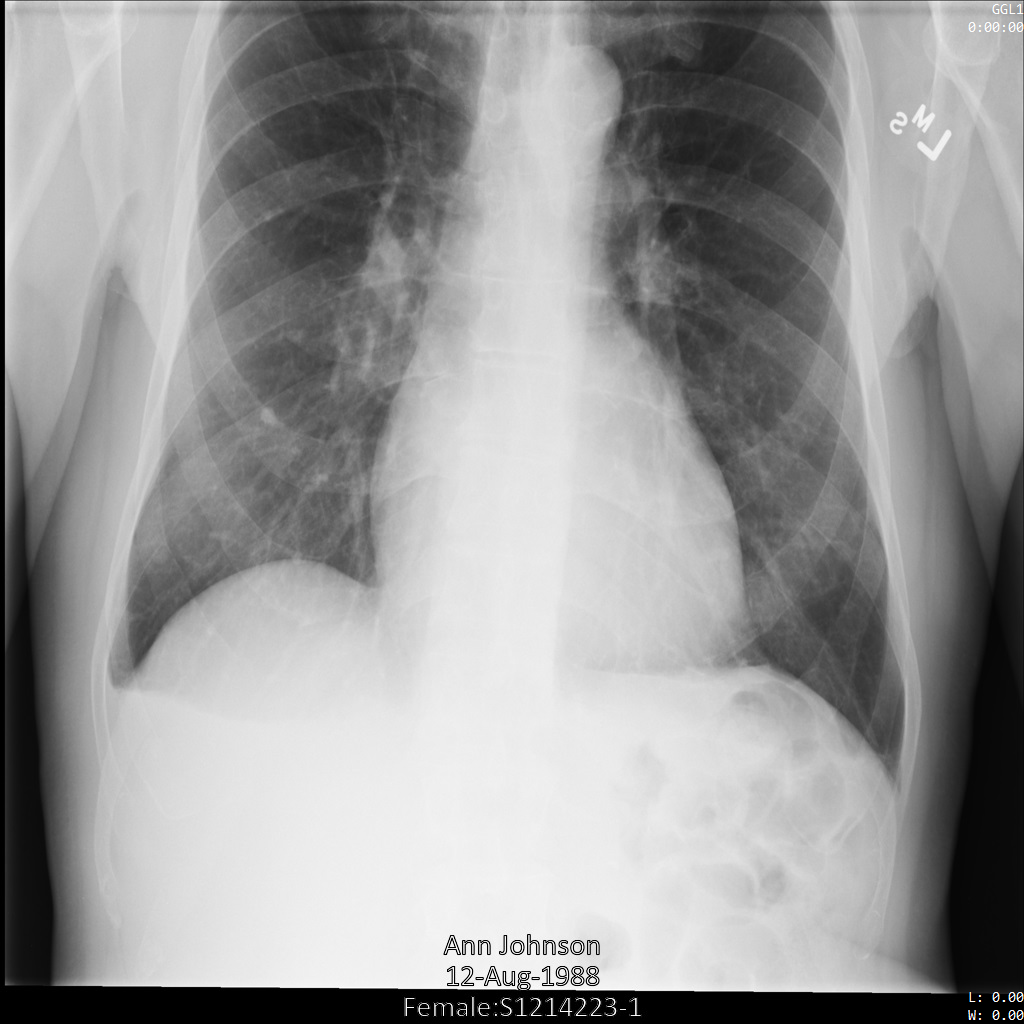

Une fois l'image envoyée à l'API Cloud Healthcare, elle apparaît comme suit. Alors que les métadonnées affichées dans les angles supérieurs de l'image ont été masquées, les informations de santé protégées qui sont incluses dans l'angle inférieur de l'image sont conservées. Pour supprimer également le texte incrusté, consultez la section Masquer le texte incrusté dans les images.

dicom_keeplist